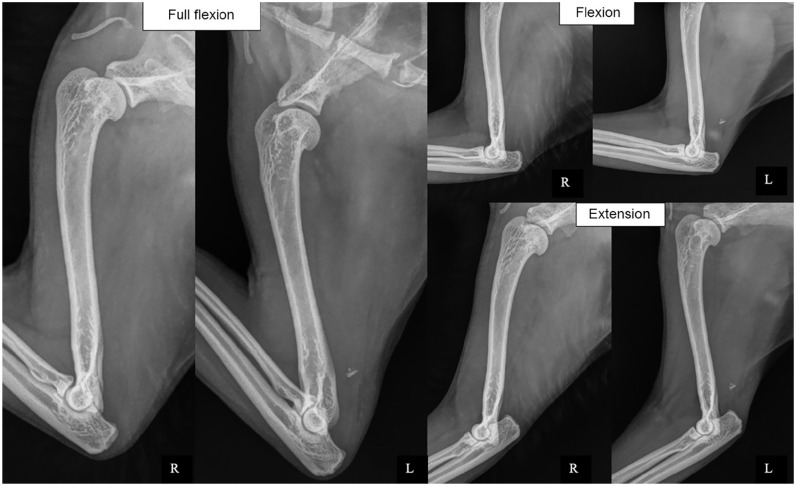

Case summary: Major avulsion of the triceps tendon insertion was diagnosed in a 7-year-old domestic shorthair cat 3 weeks after developing sudden severe weightbearing lameness of the left thoracic limb. Diagnosis was confirmed with orthopaedic, radiographic and ultrasonographic examinations. The absence of adequate bone stock prevented the use of conventional techniques for tendon reinsertion. Instead, the tendon was reattached using an ultra-high molecular weight polyethylene (UHMWPE) ExtraTape prosthesis. It was stitched into the triceps tendon and superficial fascia, then passed through a bone tunnel drilled in the olecranon and secured with a preassembled cortical button. No external coaptation was used. Although the cat experienced temporary mild lameness, pain-free and satisfactory use of the left thoracic limb was observed 4 weeks postoperatively. By 12 weeks, the cat's gait had returned to normal, with no gap between the tendon and the olecranon. The cat resumed normal gait and range of motion 8 months postoperatively.